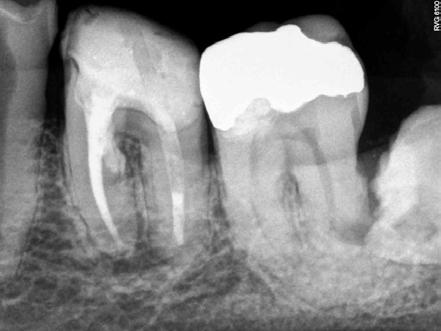

El retratamiento endodóntico comenzó con el acceso a la cámara pulpar usando una Broca Dental Predator Turbo (Angelus - Londrina - Brasil). El cemento en torno al vástago del cono de plata fue removido con una punta ultrasónica E7D (Helse Ultrasonic-Brasil) (Figura 2). Después de la exposición de la parte coronaria del cono de plata, una E5 - Punta Cónica Larga Ultrasónica (Helse Ultrasonics - Brasil) fue usada para vibrar el cuerpo del cono de plata. Aunque la baja potencia ultrasónica ajustada en un 15%, ocurrió una separación (Figura 3). Debido a la falta de adaptación del material de la obturación en el tercio apical, parte del fragmento de cono de plata fue removida de la lesión periapical.

Figura 2 - Vista del conducto obturado de la parte coronaria del cono de plata

Figura 3 - Primera separación del cono de plata

El modelo del conducto radicular se realizó utilizando Lima Reciproc R25 (VDW - Alemania) seguido por Lima Reciproc Azul RB50 (VDWAlemania). Durante el retratamiento endodóntico, se realizó una irrigación abundante con un 2,5% de hipoclorito de sodio. Después de varios intentos para quitar la parte remanente del cono de plata, otra separación ocurrió (Figura 4). La parte del cono de plata fue removida del canal. Sin embargo, el otro fragmento no pudo ser eliminado.

Figura 4 - Expulsión del cono de plata

El retratamiento endodóntico del conducto obturado fue realizado con un enjuague final con EDTA 17% pasivamente activado ultrasonicamente, seguido por obturación del conducto radicular usando conos de gutapercha con BIO-C® REPAIR (Angelus - Brasil). BIO-C® REPAIR es un nuevo Cemento Endodóntico Biocerámico Listo para Uso. Puede ser colocado de la jeringa directamente al conducto radicular. Los conos de gutapercha fueron compactados con una técnica de compactación fría vertical (Figura 5).

Figura 5 - Obturación endodóntica